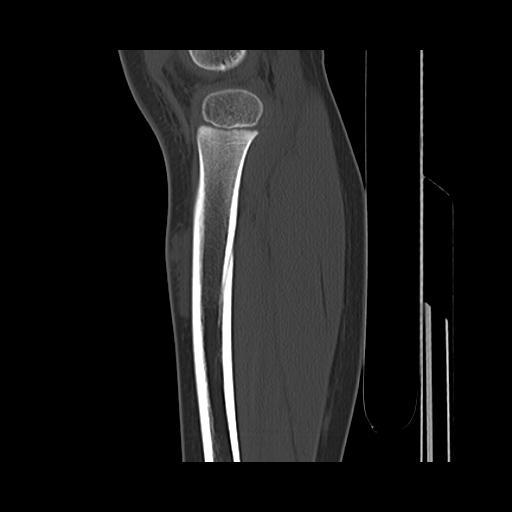

标题: PED0931:男,5岁,发现双小腿软组织肿块1年,质地中等,无 [打印本页]

标题: PED0931:男,5岁,发现双小腿软组织肿块1年,质地中等,无

多发性神经纤维瘤?

考虑多发性神经纤维瘤.

考虑多发性神经纤维瘤.支持